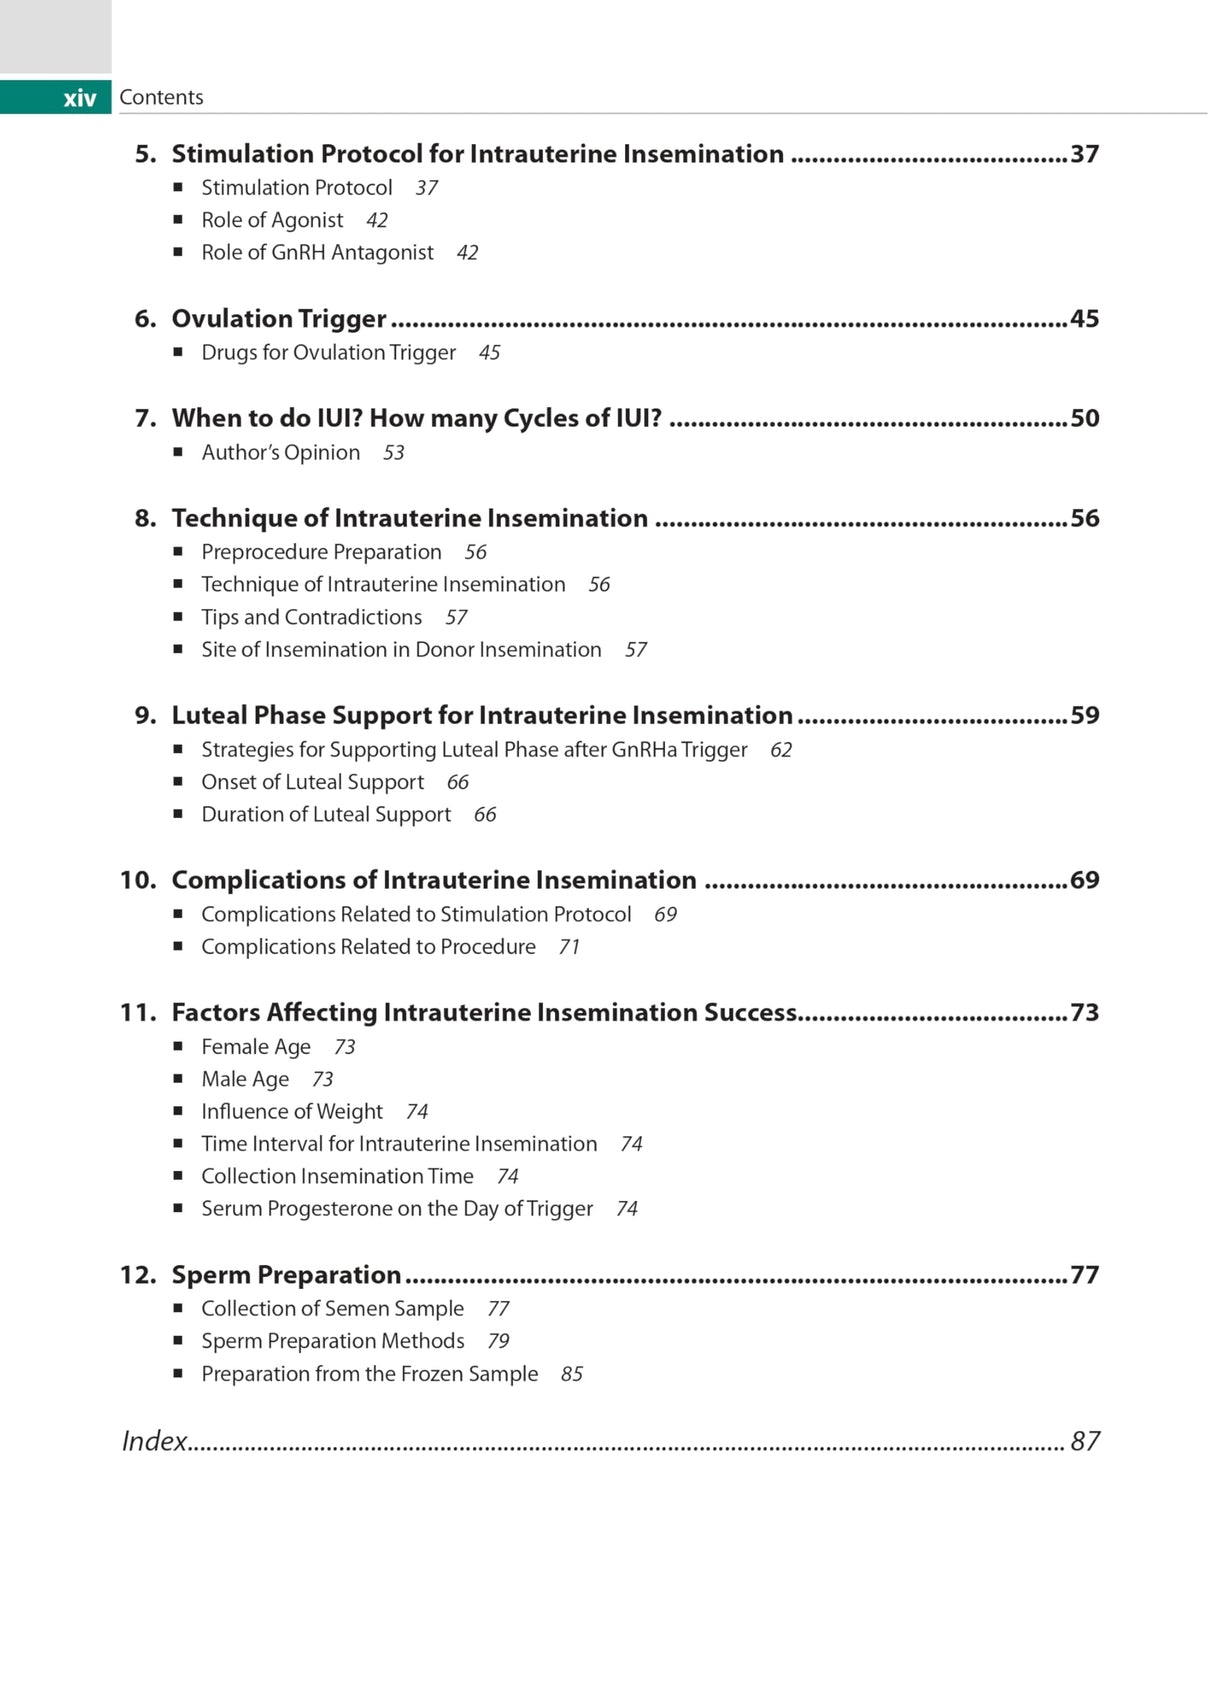

Beginning with discussion on counselling and diagnostic work-up before IUI, the next chapters cover indications and ultrasound. The following sections examine ovulation, timing of IUI, techniques, luteal phase support, complications, and factors affecting success. The final chapter discusses sperm preparation.